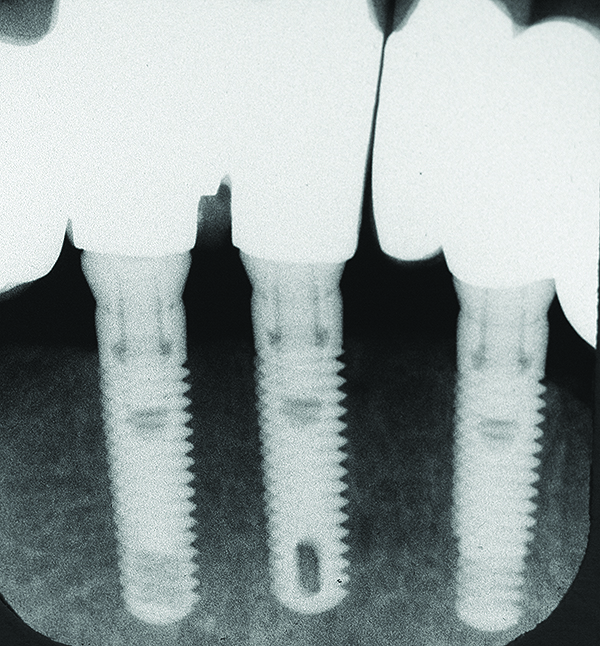

Fig 16 and Fig 17. Clinical photographs demonstrating bone loss and recession 20 years after prosthesis insertion. Initially the gingival margin covered the implant collars and threads. Fig 16: maxillary right; implants were placed at site Nos. 3 through 6. Fig 17: maxillary left; implants were placed at site Nos. 10 through 13.